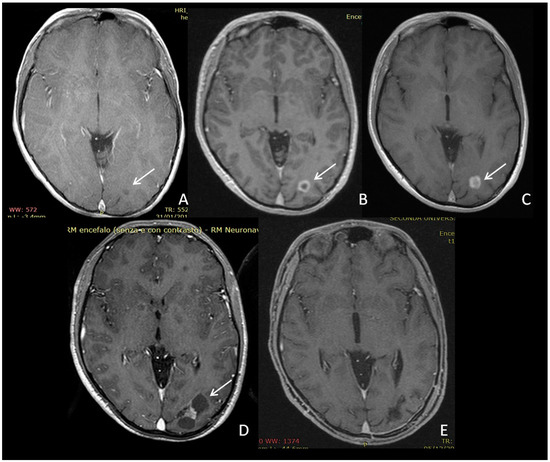

- Cakirer, S.; Karaarslan, E. Spontaneous involution of a non-optic astrocytoma in neurofibromatosis type I: Serial magnetic resonance imaging evaluation. Acta Radiol. 2004, 45, 669–673. [Google Scholar] [CrossRef]

- Leisti, E.L.; Pyhtinen, J.; Poyhonen, M. Spontaneous decrease of a pilocytic astrocytoma in neurofibromatosis type 1. Am. J. Neuroradiol. 1996, 17, 1691–1694. [Google Scholar]

- Gallucci, M.; Catalucci, A.; Scheithauer, B.W.; Forbes, G.S. Spontaneous involution of pilocytic astrocytoma in a patient without neurofibromatosis type 1: Case report. Radiology 2000, 214, 223–226. [Google Scholar] [CrossRef]

- Gottschalk, S.; Tavakolian, R.; Buske, A.; Tinschert, S.; Lehmann, R. Spontaneous remission of chiasmatic/hypothalamic masses in neurofibromatosis type 1: Report of two cases. Neuroradiology 1999, 41, 199–201. [Google Scholar] [CrossRef]

- Schmandt, S.M.; Packer, R.J.; Vezina, L.G.; Jane, J. Spontaneous regression of low-grade astrocytomas in childhood. Pediatr. Neurosurg. 2000, 32, 132–136. [Google Scholar] [CrossRef] [PubMed]